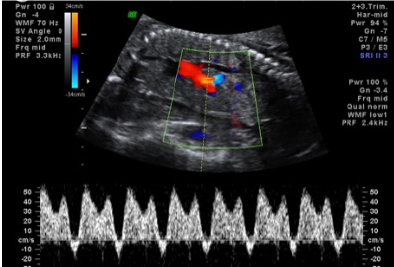

Qual estágio do CIUR?

Estagio 5 (diastole/onda A reversa de ducto venoso)